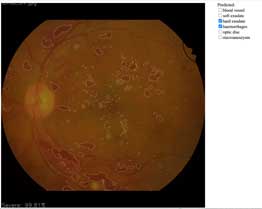

Diabetic Retinopathy

(fundus image)

- Automatic lesion detection

- Highlight lesion location

- Stage classification